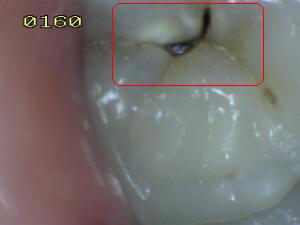

¿Determine los códigos pertinentes a cada imagen?

Click en el hipervínculo: Para comparar el resultado de su diagnóstico